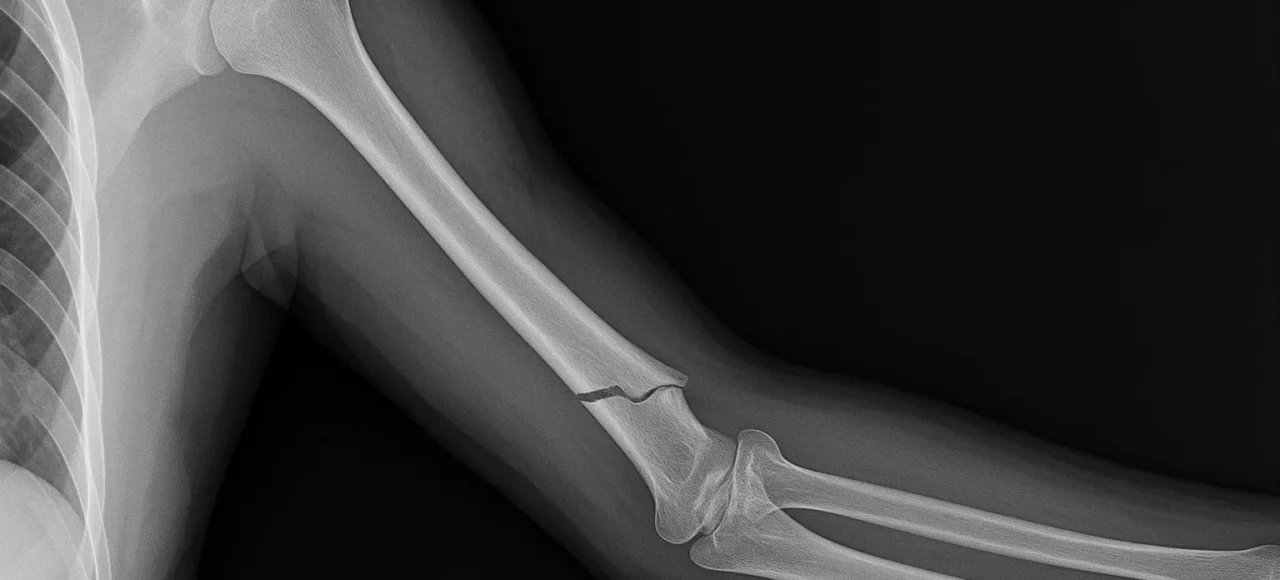

fracture du fémur

La fracture du fémur est une blessure grave qui peut survenir à la suite d’un accident, d’une chute ou d’autres traumatismes. Elle est particulièrement fréquente chez les personnes âgées, notamment celles souffrant d’ostéoporose. Cette condition affaiblit les os, les rendant plus susceptibles de se fracturer....